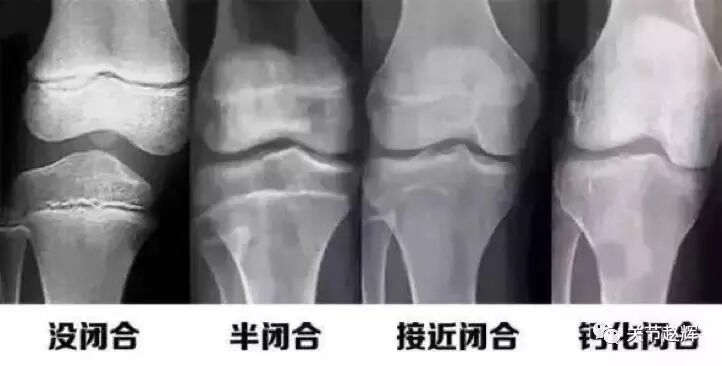

谁是长骨?比如上臂的肱骨,下肢的股骨,长和宽比起来,灰常长,通俗点说,就是大腿骨、小腿骨哥儿俩一商量,就决定了你是一米五还是一米八。长骨两端比较粗,这地方叫骨骺,在没"定型"之前,这里有个叫骺板的东西,不停地向着中间的骨干生长啊、骨化啊,让骨干变长、再变长,但这货不是一直在干活,"长大后我就成了你",青春期不再,骺板自己都骨化了,也就是骨骺闭合,个头儿也就不再长了。

如何确认自己的骺板有没有闭合?年龄小的,比如十二三岁,多半没有,至于年龄大的,只能拍个片子让骨科的帅哥们来告诉你啦。